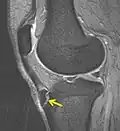

MBq Osgood-Schlatter, flecha mostrando la enfermedad -